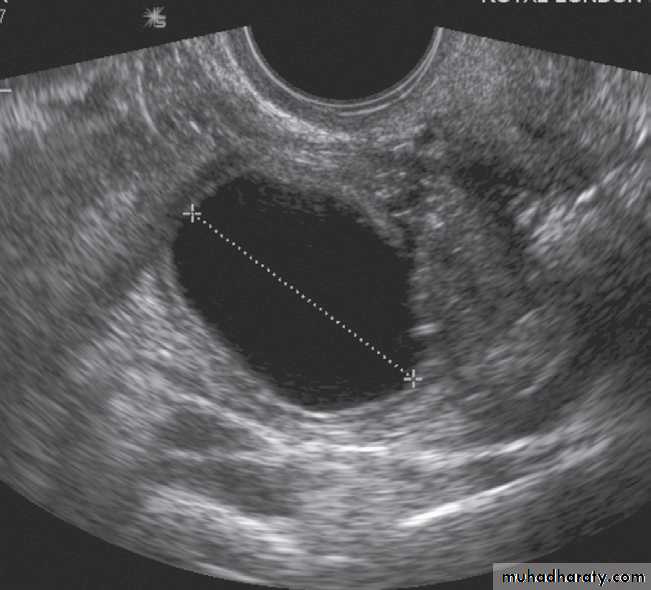

-The typical features of

polycystic ovaries on

ultrasound or MRI include

large volume ovaries

with multiple small

follicles arranged

around the periphery,

forming the appearance

of a ‘string of pearls’ .